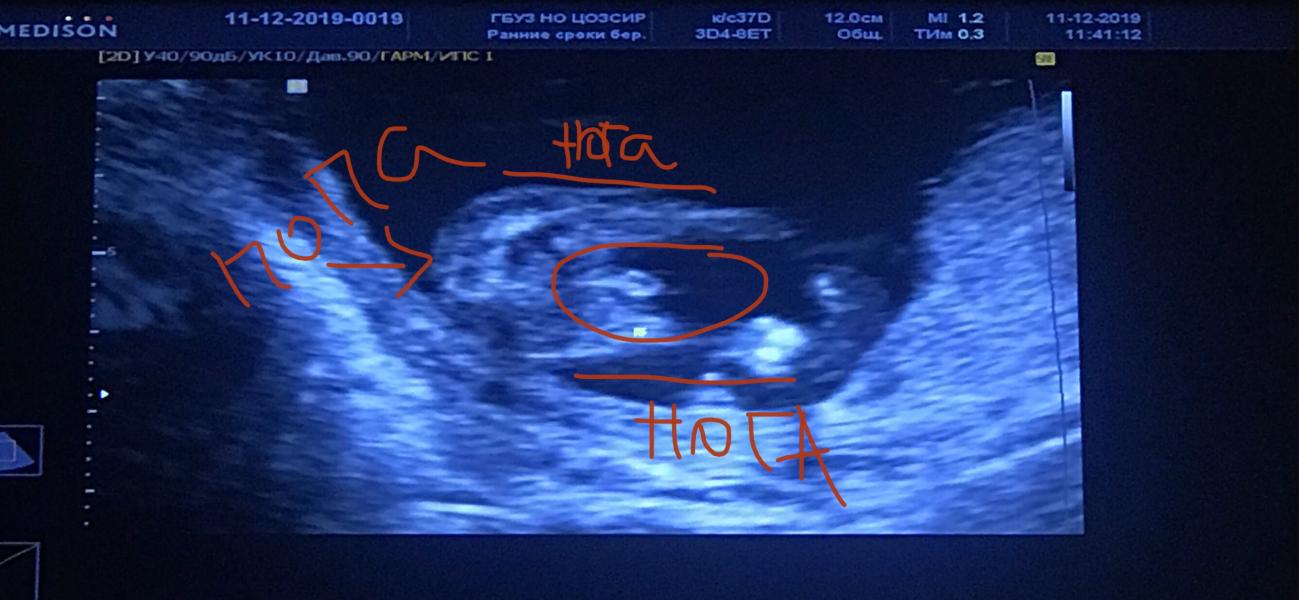

Сегодня была на скрининг, девочка 100%

По узи у меня вообще 14 недель (поздняя овуляция) думаете есть шанс на девочку ? 🙏🏻

Какой красивый болтик 😁У нас такой же -мальчик )))и это 100% . Ждали девочку , муж очень хотел малышку 🙈Я аж переживала , как ему сказать 🙃

Сходите на 3d если сомневаетесь) но видно, что пацанчик. Родите, и скажете еще, что с пацаном легче, ваш же ребенок, как воспитаете -таким и будет, характер и воспитание не следствие гендера)

Заветный писюн, как мы его ждали на каждом УЗИ😂😂